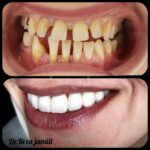

ونیر سرامیک , زیبایی , طراحی خط لبخند